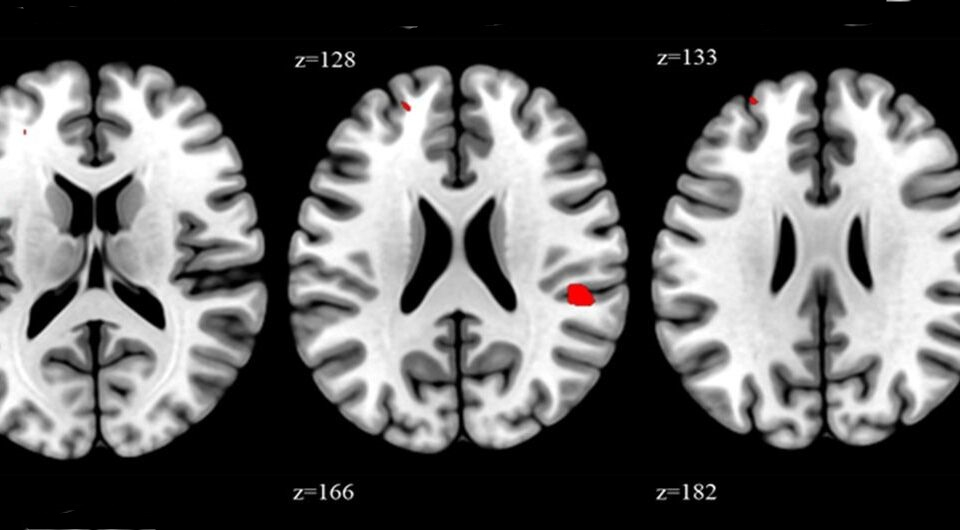

Корейские исследователи обнаружили увеличение областей мозга, ответственных за эмоциональную регуляцию, память и речь, у людей, которые регулярно работают сверхурочно. Для этого они сравнили МРТ мозга у медицинских работников, которые перерабатывают, и у их коллег, которые работают по стандартному графику. Изменения коснулись 17 областей мозга, среди которых были средняя лобная извилина, островок и верхняя височная извилина. Результаты исследования опубликованы в журнале Occupational&Environmental Medicine.